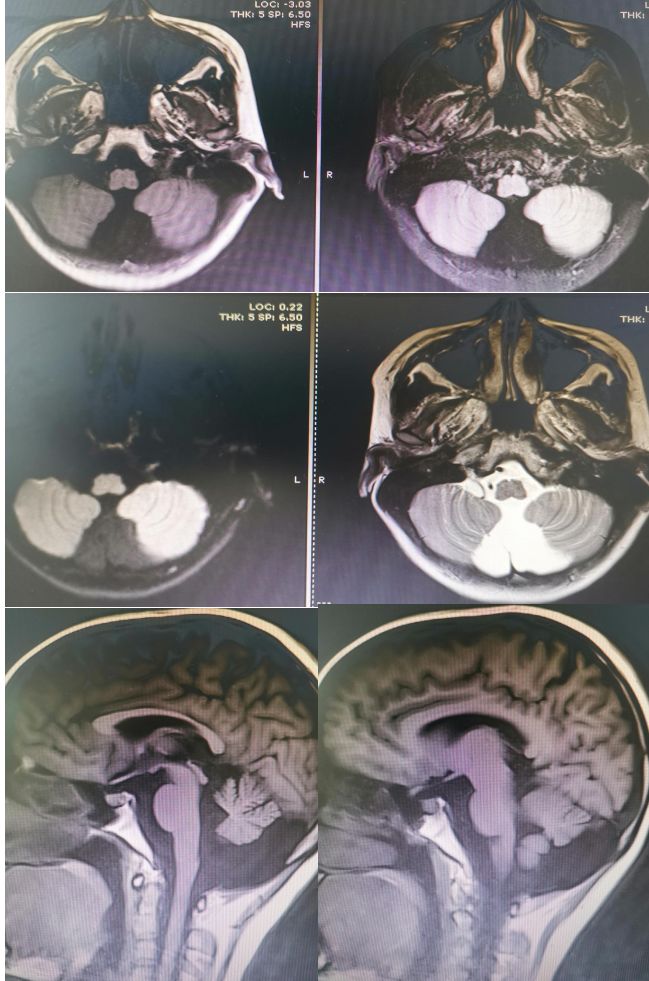

答案:Dandy-Walker畸形(变异型)

Dandy-Walker畸形典型三联征:小脑蚓部发育不良+四脑室囊样扩张+后颅窝扩大。

Dandy-Walker畸形可合并其他异常,70-90%可合并脑积水。

三联征不全,只有前两联,没有后颅窝扩大时,称为Dandy-Walker变异型。

该病例后颅窝扩张并不明显, 应该符合Dandy-Walker变异型。虽然到了周五,大家热情不减。有理有据的分析,不管是对是错,总是会有收获。